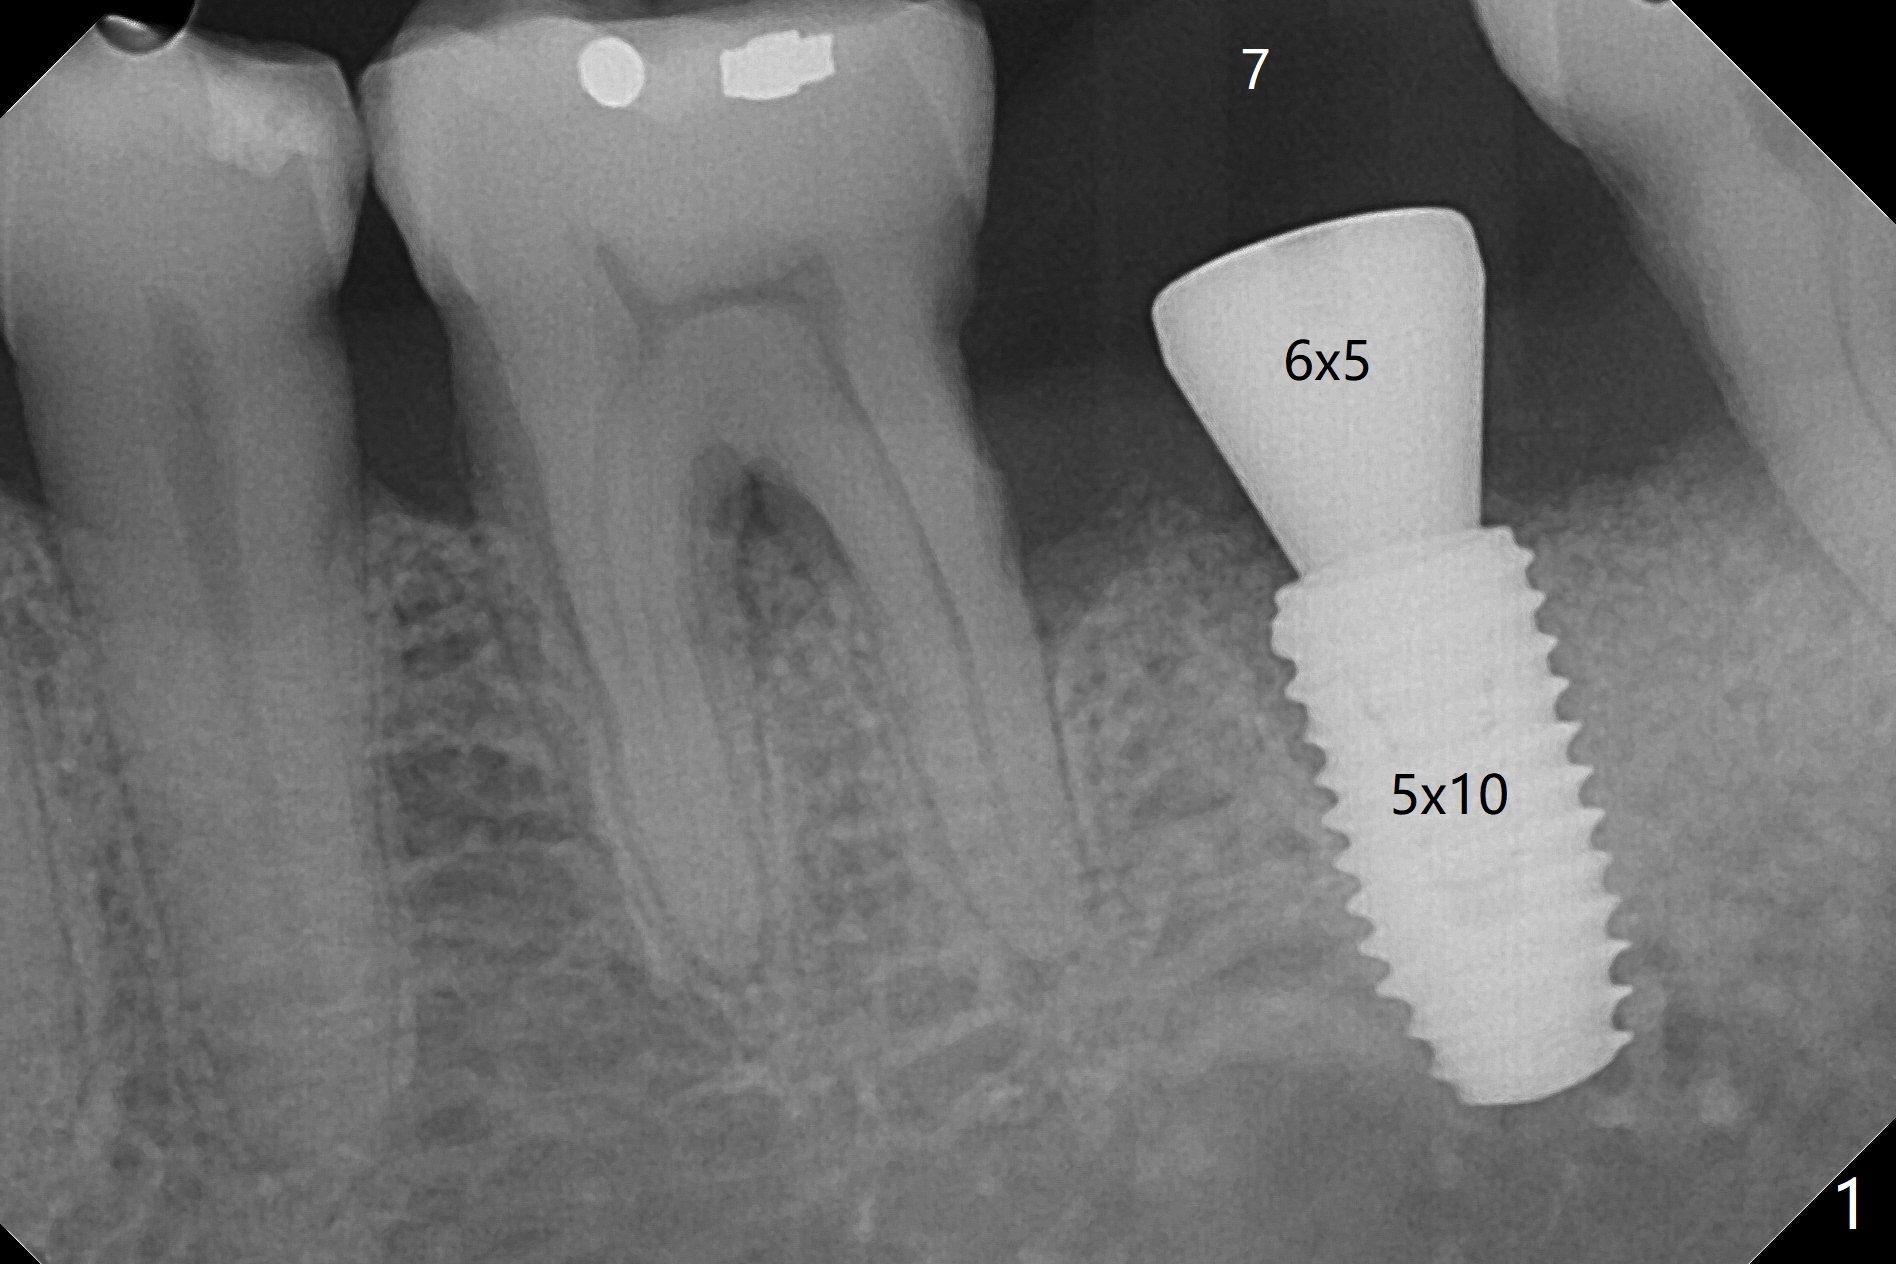

60岁男,吸烟,左下7位点保存后5个月,使用导板环形刀等常规植入5x10毫米IS植体,使用profile drill后,放置6x5毫米愈合基台(图一)。术后3个月,原来近中牙槽窝完全愈合(图二:*),放置5.5x5.7(3)毫米IBS基台,好像没有完全就位,更换4.5x7(4)毫米UF基台就位仿佛改善(图三),降低基台高度后取模。